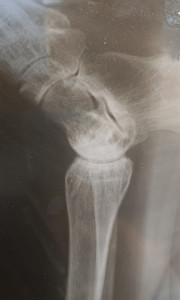

Здравствуйте. На этом рентгеновском снимке изображение получилось не очень чётким из-за бликов и неравномерного освещения и как я понимаю красное это ноготь, но перелома или выраженной трещины на видимых участках костей я не вижу. Однако для точной оценки нужны как минимум две проекции и осмотр врачом-травматологом. По одному фото плохого качества окончательный вывод сделать нельзя.

Здравствуйте, Владимир Геннадьевич, я поменяла фото в вопросе. Не могли б вы взглянуть ещё раз. Спасибо